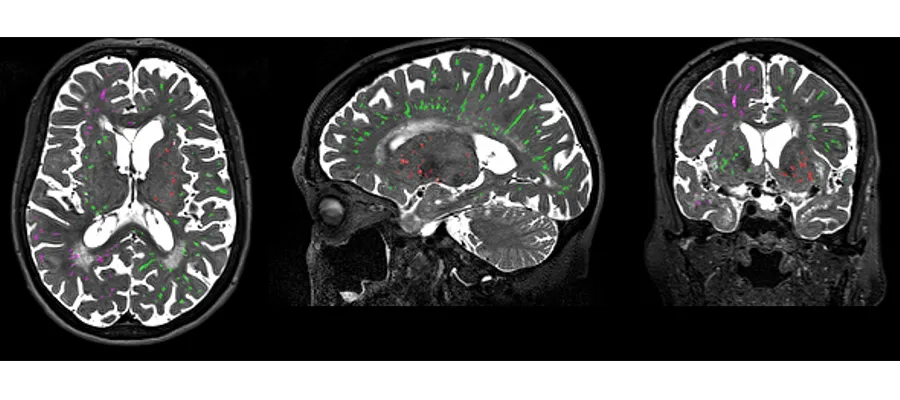

MRI brain scans

The main focus of the Centre  is to improve understanding, diagnosis and treatment of Small Vessel Diseases (SVD), which are a major cause of stroke, cognitive decline, dementia, and mobility problems.